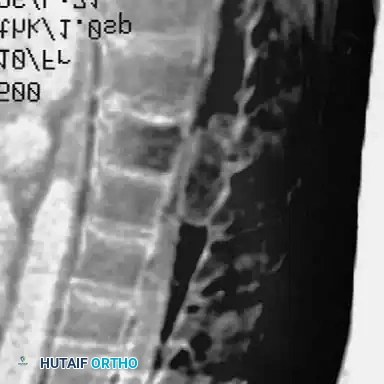

The preoperative workup for an NF-1 patient with spinal deformity must be exhaustive. The presence of intraspinal lesions—such as pseudomeningoceles, dural ectasia, or intraspinal neurofibromas (dumbbell tumors)—must be definitively ruled out before any surgical instrumentation is attempted.

Impingement of these occult lesions against the spinal cord during the correction maneuvers of instrumentation has been documented to cause acute, irreversible paraplegia.

Routine total spine Magnetic Resonance Imaging (MRI) is mandatory. Ramachandran et al. demonstrated that 37% of NF-1 patients (in both dystrophic and nondystrophic groups) harbored intraspinal and paraspinal neurofibromas, often adjacent to the convexity of the curve. While MRI is superior for evaluating cord displacement and the subarachnoid extent of neurofibromas, severe kyphoscoliotic deformities may render MRI inadequate due to artifact and complex multi-planar anatomy. In such cases, complete high-volume CT myelography in the prone, lateral, and supine positions is required to accurately map the spinal canal.

Dystrophic Kyphoscoliosis

Dystrophic scoliosis coupled with angular kyphosis represents one of the most formidable challenges in spine surgery. Patients with this pathology respond exceptionally poorly to posterior fusion alone. Consistent, long-term success is achieved almost exclusively through combined anterior and posterior (360-degree) fusions.

Neurological deficits in NF-1 patients can arise from two distinct etiologies: direct compression from an intraspinal tumor (e.g., neurofibroma) or mechanical compression from severe angular kyphosis.